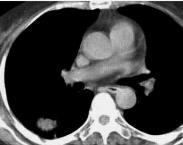

球形肺炎

• 球形肺炎

628健康網為您分享有關球形肺炎的癥狀,球形肺炎的治療方法,球形肺炎的預防知識,球形肺炎的癥狀圖片,球形肺炎吃什么藥,球...